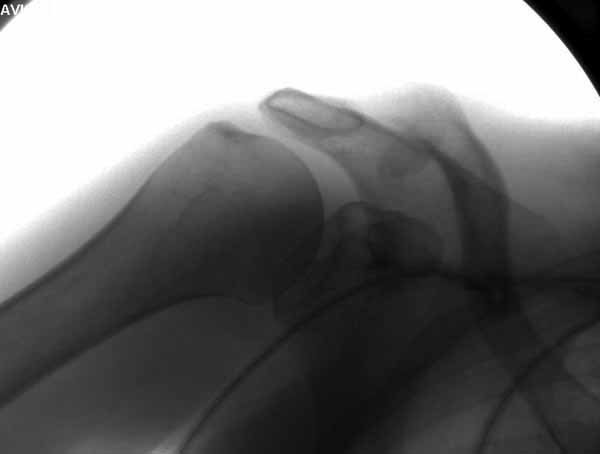

foto 3

3.JPG

14KB (15209 bytes)

|